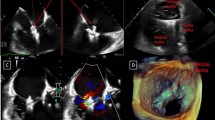

Multiple 3D-TTE views of an open TV as seen from RV aspect (a) and from RA aspect (b) and the corresponding views with the valve closed (d and e); RV inflow view (c) and a 2D multiplane reconstruction from 3D dataset (f). Note that asterisk refers to the place of TV annulus. ATL anterior leaflet, PTL posterior leaflet, STL septal leaflet, MV mitral valve, Ao aorta, RV right ventricle, RA right atrium

Assessment of TR: Moreover, real-time 3D-TTE has an increasing role in the assessment of TR (Fig. 5.6). Assessment of TV leaflets and commissures morphology, annulus size and non-coaptation distance provide important clues to etiology and mechanism of TR. Furthermore, although practically difficult, quantification of vena contracta area of TR jet on real-time colour Doppler 3D-TTE has been accomplished. The authors proposed new cut-off values for TR severity: 0.5 cm2 for mild, 0.5–0.75 cm2 for moderate, and >0.75 cm2 for severe TR [4]. However, these values need to be prospectively validated in a larger external population. Respiratory variation of TV jet regurgitant orifice area has been shown on colour Doppler 3D-TTE, as well as other TR parameters on 2D-TTE [5, 6].

Visualization of different etiologies and mechanisms of TR on real-time 3D-TTE : (a) a long-axis and (b) a short-axis enface TV view as seen from the RV aspect, a pacemaker lead (arrow) restricts TV leaflets from closing. (c) and (d) are from a patient with a prolapse of the posterior leaflet of the TV with elongated chordae as seen from RV aspect with TV open (c) and RA aspect TV closed (d). The arrow points to incomplete TV coaptation due to prolapsed posterior leaflet. Image (e) shows an enface view of TV, as seen from the RV aspect, with a tear in the TV leaflets (arrow) after repeated biopsies in a patient with a heart transplant. Image (f) shows lack of TV leaflets coaptation (arrow) due to carcinoid disease in enface RV view. ATL anterior leaflet, PTL posterior leaflet, STL septal leaflet, PM pacemaker lead, LV left ventricle